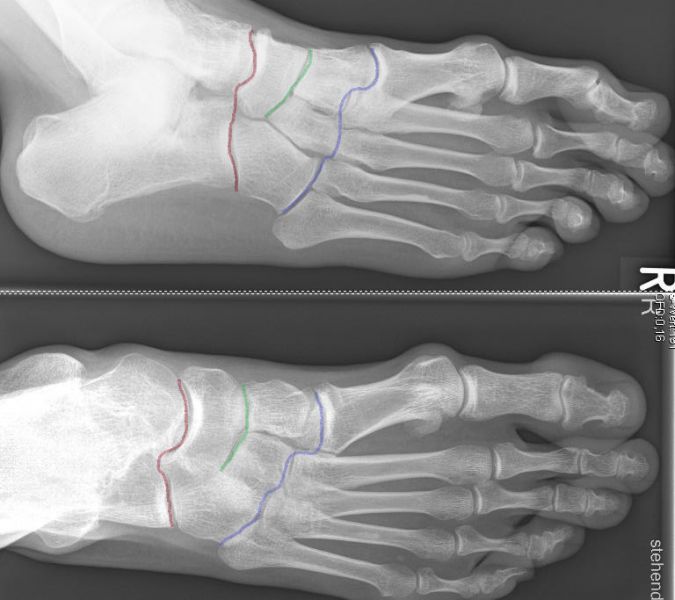

Unter den Mittelfußbereich fällt die Lisfranc- (blau), die Bona-Jäger- (grün) und Chopart- (rot) Gelenkreihe

Die Lisfranc-Gelenkreihe wird aus den Ossa cuneiformia/Os cuboideum und den jeweiligen Metatarsalia gebildet. Die Bona-Jäger-Gelenkreihe liegt zwischen dem Os naviculare und den Ossa cuneiformia. Die Chopart-Gelenkreihe wird aus Talus/Calcaneus und Os naviculare/Os cuboideum gebildet. Vor allem ist die Lisfranc-Gelenk-Linie von degenerativen Veränderungen betroffen, hierbei häufiger die mediale Säule, also die Tarsometatarsal-Gelenke I-III.

Die Tarsometatarsal-Gelenke I-III liefern maximal 7 Grad Beweglichkeit in der sagittalen Ebene 1. Viel mobiler zeigt sich die laterale Säule mit dem vierten und fünften Tarsometatarsal-Gelenk, diese sind wichtig für die Balance und Anpassung des Fußes auf unebenem Boden.